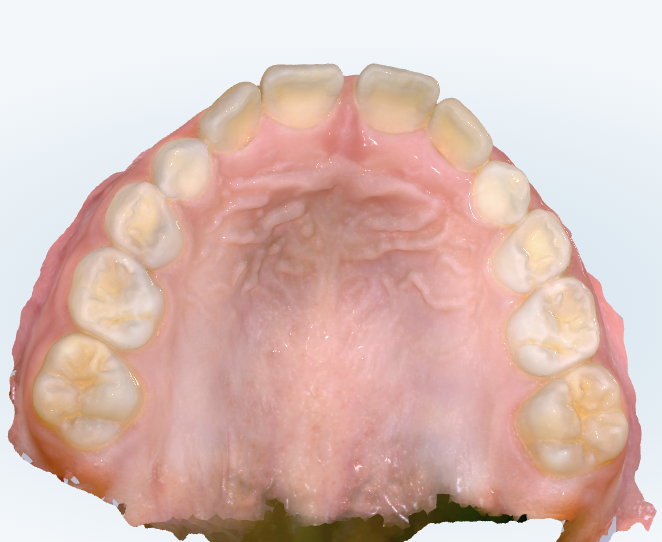

初診時の画像診断

前歯の咬み合わせが深いため、下の前歯があまり見えません。

ガタガタは少ないです。